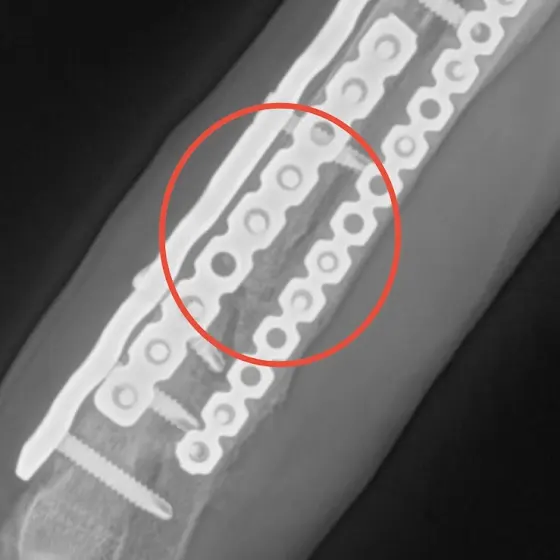

[3차수술] 현미

단체 스텝이면서 현미의 임보가족으로 현미의 수술 후 회복사진을 보니 가슴이 미어집니다.

🆘현미 예상 수술비 800만원 이상

현재+캐스퍼 모금액 대략 200만원 조금 넘어요. 도와주세요

현미는 번식장에서 태어나 펫샵 진열장에 전시되어 운좋게도 가족을 만나 집으로 갔지만 결국 덩치가 커지면서 파주의 공장 한켠에 버려졌습니다.

현미는 정말 운이 좋게 대표님이 현미의사연을 듣게되었고 아픈다리의 어린 아이를 공장 방치견으로 살게 둘수없어 리버큐의 가족이 되었습니다.

다리가 아픈친구라 쉼터생활이 힘들어서 저희집에서 지내며 치료후 미국으로 떠날 아이였지만 현미의 다리는 나날이 상태가 안좋아졌고 2차 병원 여러군데에서 진료를 보았습니다.

아직 어린 아기라 성장판이 있었기때문에 진통제를 먹으며 견뎌오다 드디어 기다리던 1차 수술을 했지만 실패로 돌아왔고 한달 후 2차 수술 역시 실패였습니다.

사고칠나이에 그냥 조용히 누워 자는 안쓰런 아이입니다. 우리 현미가 3차 수술을 마지막으로 더이상 수술대에 눕는일이 없길 바랍니다.